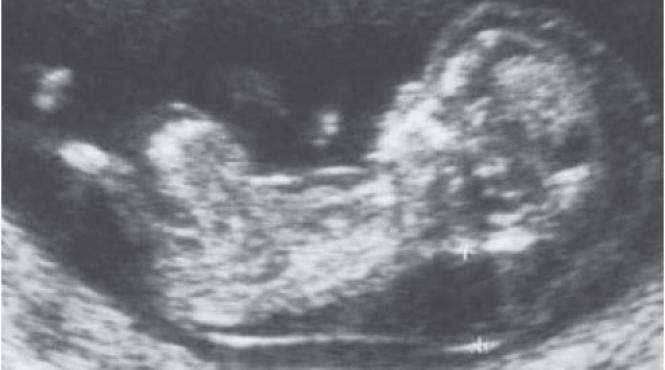

Caz ''excepţional'' în Franţa: un fetus şi-a salvat viaţa şi pe cea a mamei în urma unei rupturi uterine